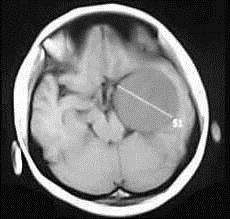

问题 女,36岁,抽搐半年,近10余天头痛加重,磁共振检查如图,选择最可能的诊断()

选项 A.胶质瘤 B.脑膜瘤 C.动静脉畸形 D.海绵状血管瘤 E.蛛网膜囊肿

答案 B